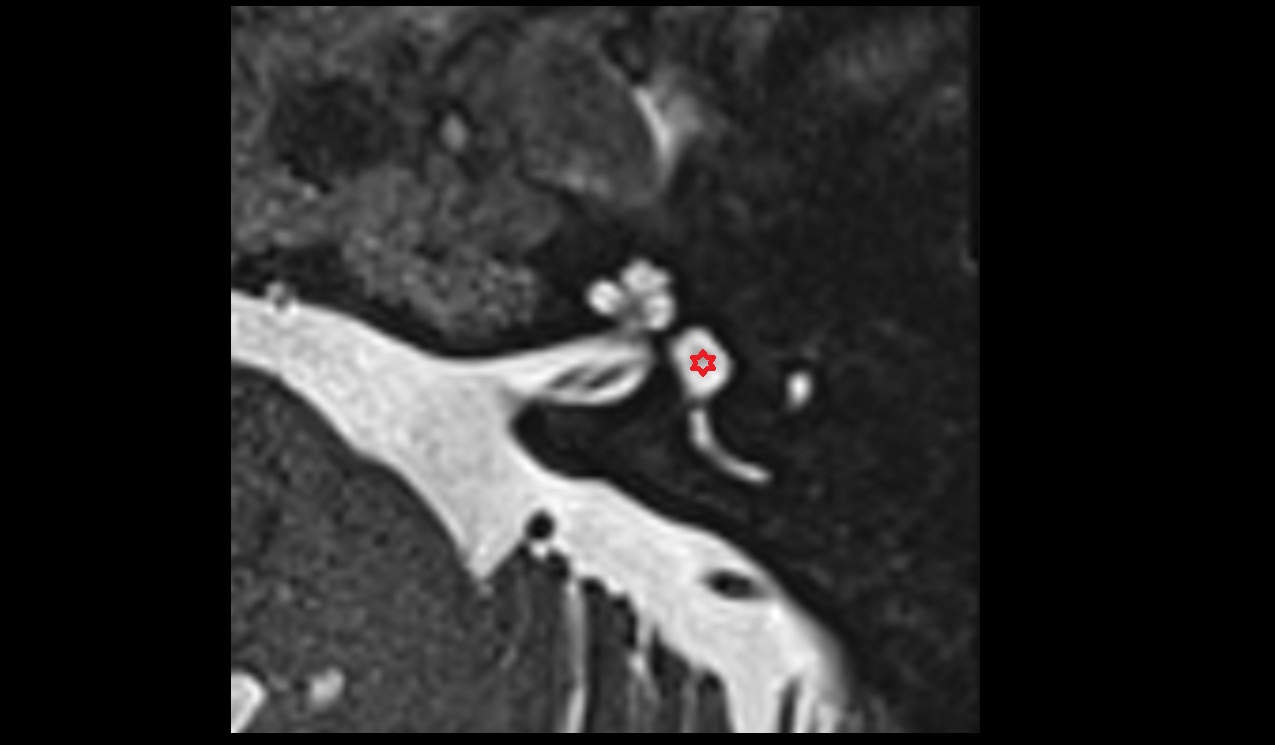

- Anterior Choroidal Artery